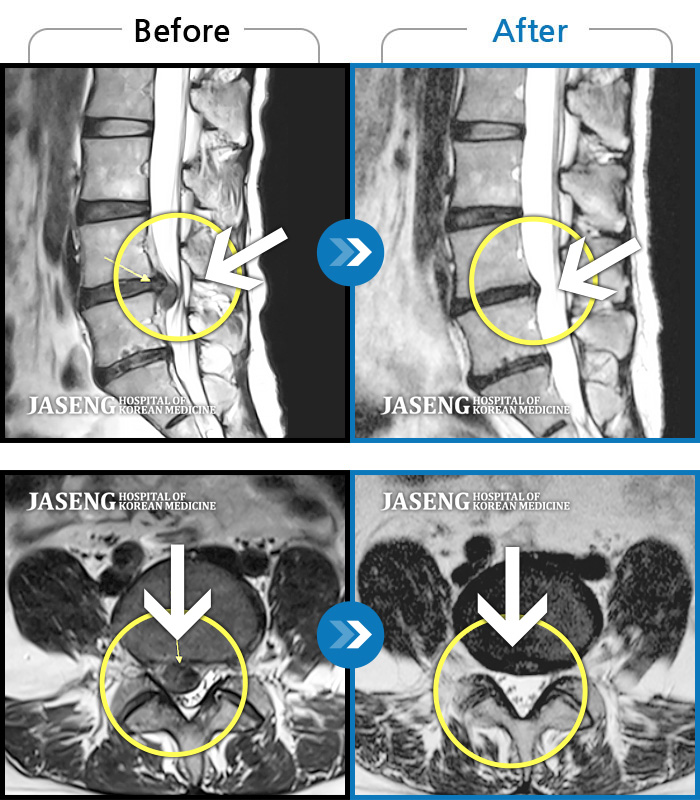

40대 초반 여성 환자인데요,, 처음 선생님 뵈었을 때에 1번,4,5번허리디스크 증상도 증상이지만,

본인 나이에 비해서 10~15년정도 퇴행이 많이 되어있어서 전체적으로 관리가 많이 필요하다고 설명해주셨구요,,

그당시 원장님진료실에서 보았던 저의 엠알아이사진이 아직도 생생히 기억이 납니다 ^^

뼈부분의 색이 왜저렇게 검냐고 여쭈어 보았더니, 말씀주신데로 "퇴행이"많이 되어서 그렇다고 설명해주시면서,,